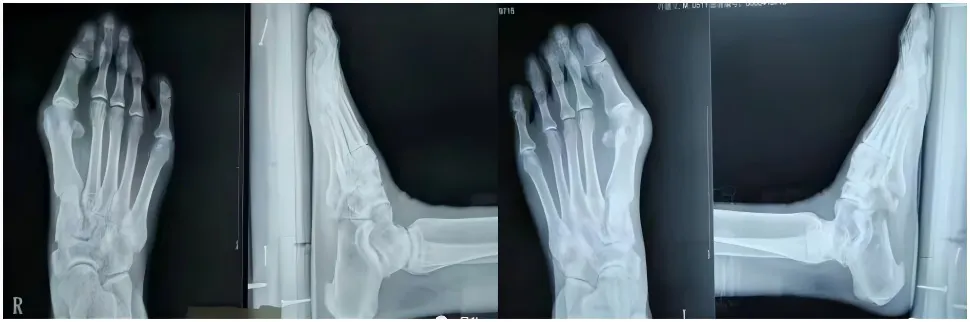

术前术后对比图

术前术后X光片对比图